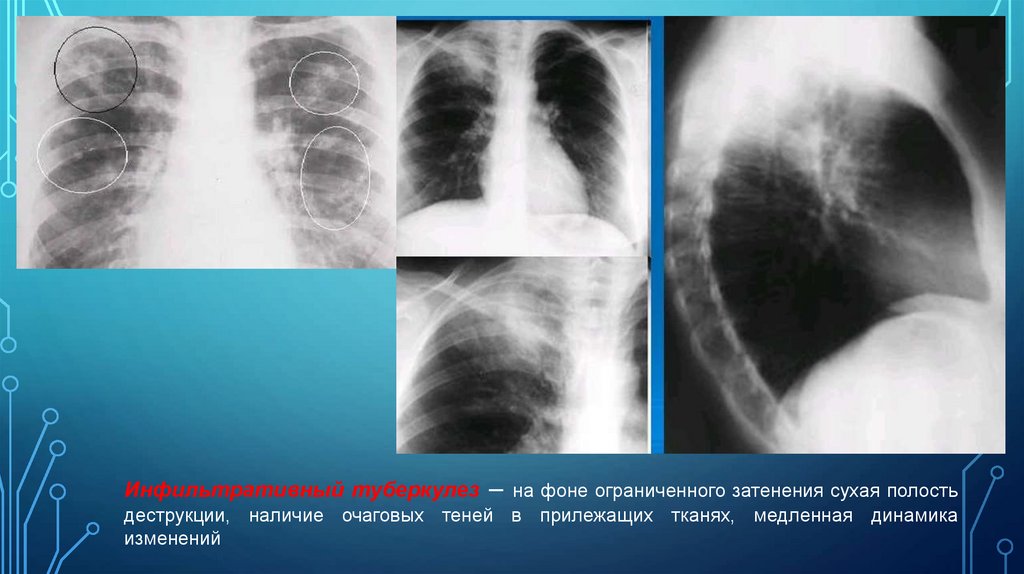

В) Инфильтративный туберкулез – на фоне ограниченного затенения сухая

полость деструкции, наличие очаговых теней в прилежащих тканях, медленная динамика

изменений

Инфильтративный туберкулез – на фоне ограниченного затенения сухая полость

деструкции, наличие очаговых теней в прилежащих тканях, медленная динамика